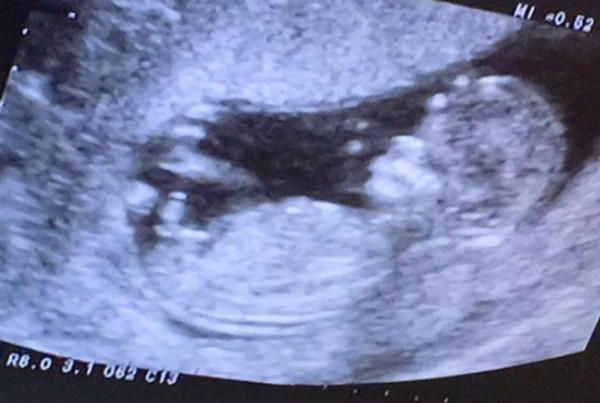

在B超孕期产检中,当屏幕上那个蜷缩的小小身影展现出双腿之间的画面时,任何一点细微的凸起或阴影,都可能被赋予特殊的含义。坊间流传着一种说法:B超看到两腿间有凸起,那就是男孩;平平的,那就是女孩。然而,如果怀的是女孩,B超下她的两腿中间也会出现凸起的情况。这个问题看似简单,背后却涉及超声影像的原理、胎儿发育的阶段特点,以及那些容易被忽略的干扰因素。

B超不是照相机,它照出来的是一张由无数个灰白光影组成的“二维切片图”。医生需要根据这些光影的形态、位置、回声强弱来判断胎儿的结构。而咱们这些外行,很容易被某一个角度的假象带偏。尤其是胎儿在肚子里动来动去,体位千变万化,再加上脐带、手指、甚至羊水的干扰,两腿之间出现一个暂时的凸起,真的太常见了。

既然凸起不能作为性别的“铁证”,那专业的B超医生到底是怎么分辨男女的呢?其实,医生看的不是简单的“有”或“没有”,而是生殖器的具体形态特征。

而女宝宝的B超影像特征,业内常说的一个词叫“三条线”。所谓三条线,指的是两侧大阴唇和中间缝隙形成的两条强回声亮线夹着一条低回声暗线,看起来像是两片面包夹着心,也有人说像是一个“汉堡包”的切面。随着孕周增加,女宝宝的大阴唇会变得更饱满,有的医生形容像“橘子瓣儿”,有的说像“米其林轮胎”的褶皱。所以,如果在B超图像上没有看到明确的“茶壶”轮廓,而是看到比较典型的平行线结构,那大概率就是女宝宝。